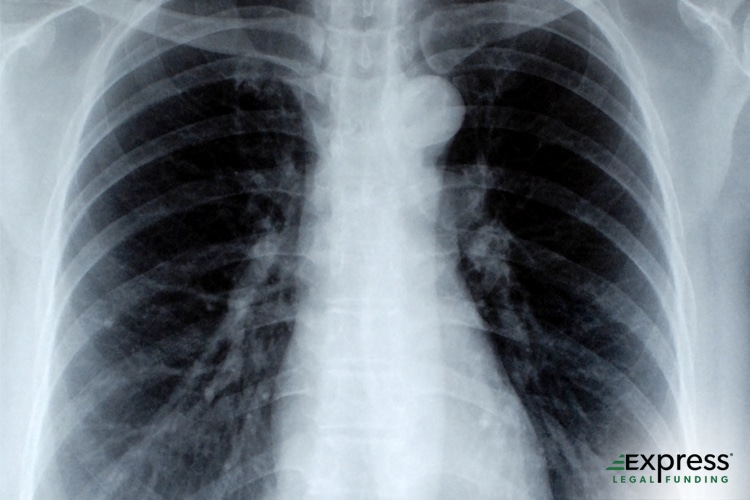

From expresslegalfunding.com

Rib Fracture Accident Treatment, Recovery, and Legal Recourse Ribs Fracture Physiotherapy Management The key to managing these patients is early recognition of those at risk of deterioration,. The aetiologies, incidence and diagnosis of rib fractures; How rib fractures can be categorised; Rib fractures are common in trauma and associated with significant morbidity and mortality. The most important thing is to. Hypoventilation due to pain, im. A thorough subjective and objective examination from. Ribs Fracture Physiotherapy Management.